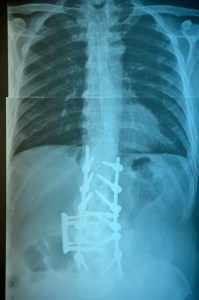

Doctor Convinces Patients to Undergo Dangerous and Unnecessary Surgeries

An Ohio spine surgeon faces federal charges of health-care fraud and making false statements, in addition to numerous medical malpractice claims, because he allegedly convinced patients to have surgical procedures that they did not need. Dr. Abubakar Atiq Durrani is accused of telling some of his patients that without spinal surgery “they risked paralysis or that their heads would fall off if they got into car accidents.” There is even some doubt as to whether or not Mr. Durrani attended medical school. To date, about 60 lawsuits have been filed against him.

All surgeries carry risks. Putting a patient in harm’s way purposely violates Tennessee and federal law, as well as the Hippocratic Oath. An unnecessary surgery can cause an infection, a heart attack, a stroke, paralysis or even death. Mr. Durrani’s gross negligence could have cost patients their lives, and it is only sheer luck (or a miracle, if you prefer) that no one died at his hands.